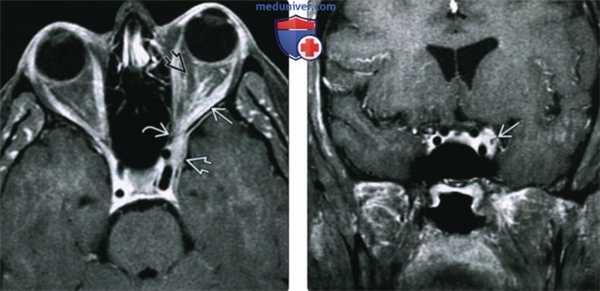

(Слева) При МРТ Т1ВИ FS c КУ в аксиальной проекции у пациента с болезненным экзофтальмом определяется объемное образование глазницы, поражающее наружную прямую мышцу и ткани внутри мышечного конуса. Обратите внимание на распространение идиопатического воспаления через верхнюю глазничную щель в переднюю часть кавернозного синуса.

(Справа) При МРТ Т1ВИ FS с КУ в корональной проекции у этого же пациента видно, что объемное образование распространяется в полость черепа и прорастает в левый кавернозный синус. Распространение идиопатического воспаления глазницы в кавернозный синус - наиболее часто встречающаяся локализация внеглазничного поражения.